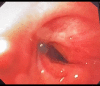

BACKGROUND The role of tracheostomy during the coronavirus disease 2019 (COVID-19) pandemic is still to be determined, and the complication rate of the tracheostomy in COVID-19 patients is still unknown. Postintubation tracheal stenosis is a well-known risk of prolonged endotracheal intubation, but it is too early to define the existence of any difference among the COVID-19 cohort of patients and non-COVID-19 patients. This report is of 2 cases of COVID-19 pneumonia that required tracheostomy and prolonged endotracheal intubation, which were followed by delayed tracheal stenosis. CASE REPORT Case 1. A 54-year-old male was admitted to our hospital (Biella, Italy) for severe acute respiratory syndrome coronavirus-2 (SARS-CoV-2) infection. The patient underwent orotracheal intubation, progressively improving his breathing function, and was discharged after 20 days. Ten days later, the patient presented with severe respiratory distress. Computed tomography (CT) scan and bronchoscopy showed signs of tracheal stenosis. We administered intravenous steroids for 10 days. The patient showed increasing improvement in his breathing function and was discharged with no other signs of respiratory distress. Case 2. A 43-year-old male was admitted to our hospital for SARS-CoV-2 infection. The patient underwent orotracheal intubation, progressively improving his breathing function, and was discharged after 25 days. Eighteen days later, the patient came to our emergency room with severe respiratory distress. CT scan and bronchoscopy showed signs of tracheal stenosis. The patient had to undergo tracheal resection. CONCLUSIONS The 2 cases presented in this report have shown that even when patients recover from severe COVID-19 pneumonia requiring tracheostomy and mechanical ventilation, tracheal stenosis should be recognized as a potential complication and careful follow-up is required.